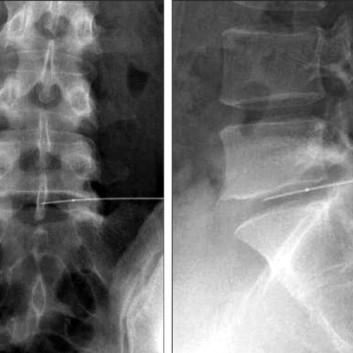

풍선 확장 유착 박리술은 꼬리뼈에 있는 척추관으로 통하는 구멍으로 직경 1mm 미만의 카테터를 삽입하여 디스크와 협착증이 있는 부위까지 접근시켜 풍선 확장으로 척추관을 넓혀주고 협착 부위의 유착을 녹이는 효소제와 염증과 부종을 줄여주는 항염증제를 주입합니다.

허리디스크와 요추 척추관 협착증, 급성 및 만성 요통, 발저림증, 전후방전위증, 척추 수술 후 지속 되는 통증, 목디스크와 경추 척추관 협착증